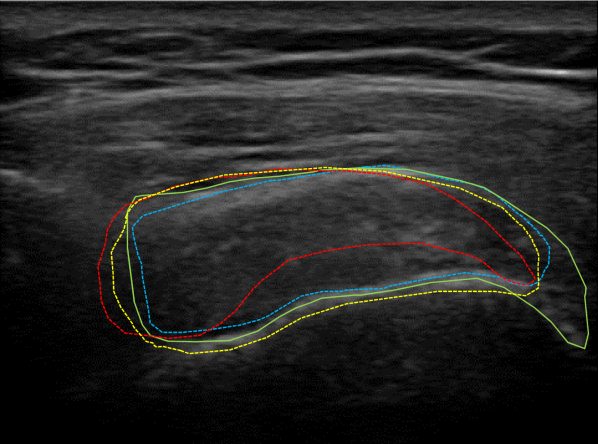

Qualitative performance and advantage of our proposed segmentation method over two different methods are presented in Fig. 8. In this figure, original US images of three cases taken from the SST data-set are shown in the first row and the second row depicts the raw predictions of the NASUNet model. On each image, boundaries of the segmentation maps derived from the ground truth (radiologist annotation), proposed method (NASUNet), DeepLab V3 network (the second best performing method in Table 1), and Active Appearance Model (AAM, the worst-performing method based on Table 1) are drawn with green, blue, yellow, and red colors, respectively. It is evident from Fig. 8 that the delineation by our method is closer to the ground truth annotation in comparison with other methods, which indicates the power and efficiency of NASUNet in SST boundary detection. In all of the subsequent tendinopathy recognition experiments, resulting segmentations from the best performing model (NASUNet) are utilized.

Figure 8: Visualizing the SST boundaries resulted from different segmentation methods for three different cases in the first row. Boundaries of ground truth, proposed NASUNet model, DeepLab v3 network, and AAM method are overlaid on their related images with green, blue, yellow, and red colors, respectively. The second row illustrates the raw segmentation prediction maps from NASUNet.